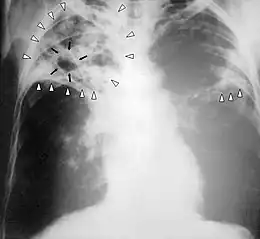

Diagnostic radiologique

La modalité de diagnostic radiologique se révèle très utile et indiquée comme étant un examen de première intention en cas de tuberculose pulmonaire et ostéoarticulaire[77]. Cela est justifié par les images radiologiques plus ou moins spécifiques à la tuberculose. La littérature rapporte que la spécificité varie de 27 à 81 % selon l’étude. Les imageries idéales et révélatrices de la tuberculose répondent à certains attributs dont le premier est lié au siège. En raison de l’affinité que les BK ont envers les régions aérées, la lésion radiologique est souvent observée dans les parties hautes des poumons. Néanmoins, l’image radiographique peut contenir différentes formes :

- infiltrat : traduisant des lésions débutantes de l’infection via une opacité peu dense, hétérogène et étendue ;

- nodule : granulome de taille variable, isolé ou groupé ;

- tuberculome : nodule isolé pseudotumoral ;

- caverne : excavation par perte de substance au sein d’un infiltrat, aux parois épaisses.